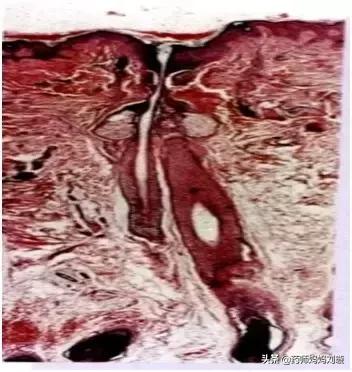

上图为粉刺的病理图片,粉刺进一步发展就成为*疮痤**。